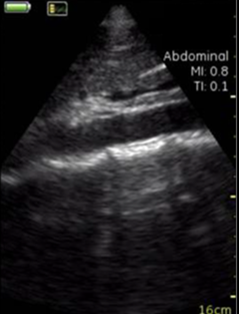

Vscan临床图片 腹部